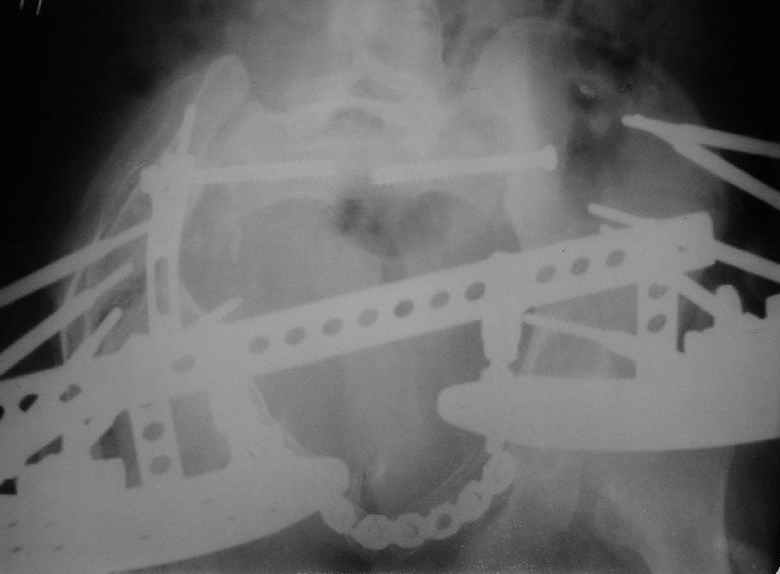

Уважаемые коллеги, вашему вниманию предлагается продолжеие истории лечения больной с двусторонней деформацией таза . Итак, 26.01.05 была выполнена остеотомия правой подвздошной кости, низведение правой вертлужной области, остеосинтез правой подвздошной кости пластиной, чрескостный остеосинтез аппаратом таз-бедро.  Снимок после первого этапа | После заживления раны и стабилизации общего состояния 22.02.05 была выполнена реконструкция переднего отдела таза, синтез лонных костей пластиной, опора с бедра демонтирована, выполнено введение илиосакральных винтов с обеих сторон. В настоящее время рана зажила первичным натяжением, больная ходит с двумя костылями без опоры на правую нижнюю конечность. С интересом ждем ваши комментарии.